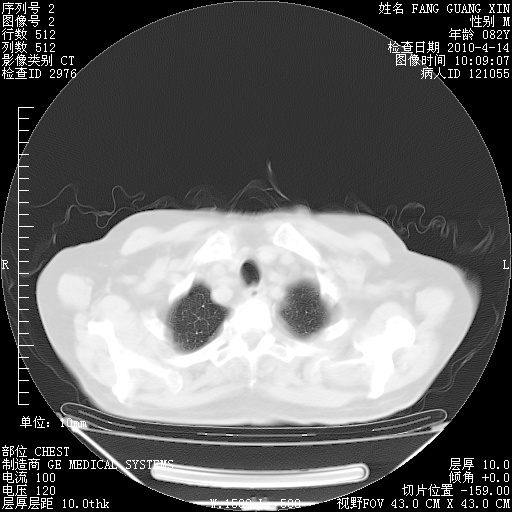

4月14日肺部CT

23.JPG

24.JPG

25.JPG

26.JPG

肺部CT平扫未见异常。